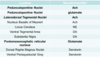

The medial & anterior nucleus of the thalamus is supplied by what arteries?

•Thalamoperforating

•Thalamogeniculate

•Inferior Thalamic

•Postero-medial choroidal